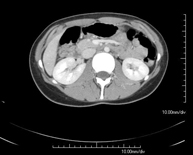

- Abdomen CT

Diagnostic test that involves obtaining high-definition anatomical images of the abdomen (liver, gallbladder, bile duct, pancreas, spleen, stomach, intestines, kidneys, vascular structures, bladder, uterus and ovaries, etc.) using CT (computed tomography) equipment. These images are then studied at a workstation capable of producing two-dimensional reconstructions in different spatial planes, and also 3D (volumetric) reconstructions. Most studies require the use of iodinated contrast to improve image definition.